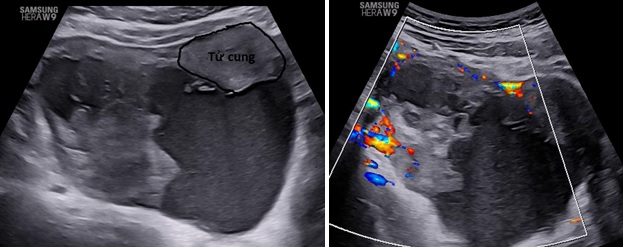

– Siêu âm: Tử cung và 2 buồng trứng bình thường. Ở cùng đồ sau có cấu trúc echo kém không đồng nhất dạng hình ống, có vách ngăn dày thông nhau, kích thước # 84x 89x 37 mm, bờ trong thành u không trơn láng, bên trong có nhiều mảng echo kém dạng mô đặc, tăng sinh mạch máu mức độ 2. Bụng và cùng đồ: không dịch.

– Chẩn đoán siêu âm: Huyết tụ thành nang. Chẩn đoán khác: áp xe phần phụ.

Hình 3: Siêu âm ngã bụng thang xám cắt dọc và ngang cho thấy khối u nằm mặt sau tử cung lan qua hai bên hố chậu.

Hình 4: Siêu âm ngã âm đạo thang xám cho thấy khối u hình ống ở cùng đồ sau nhiều vách ngăn dày thông nhau.